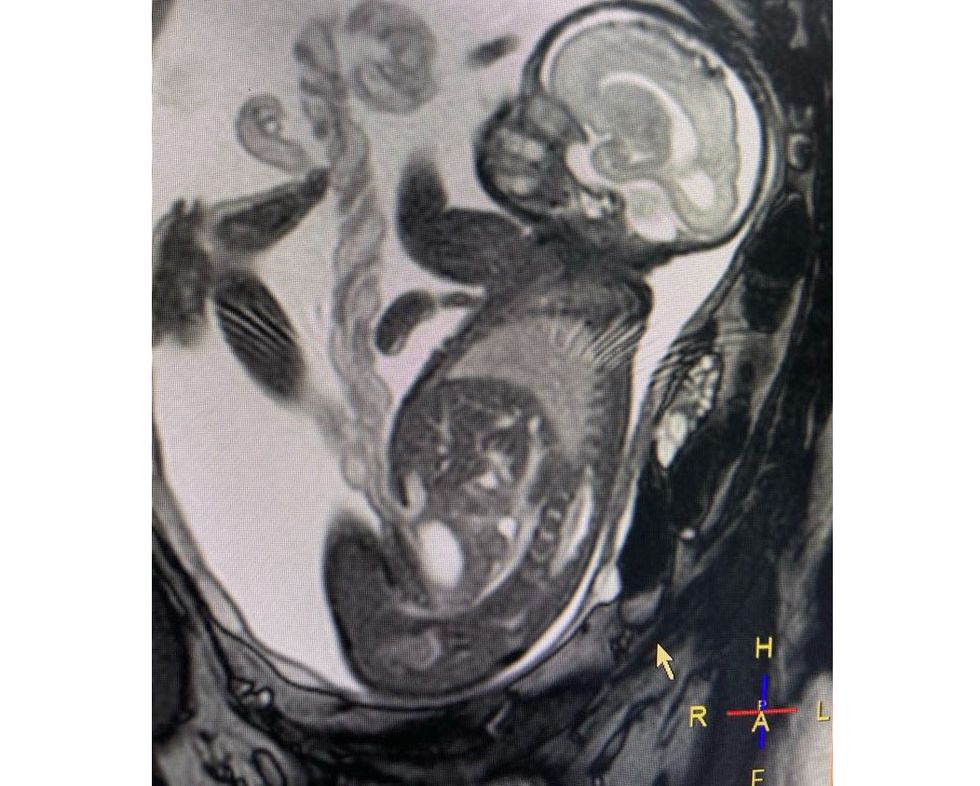

Rezonanca magnetike e fetusit për diagnozë më të saktë dhe një shtatzëni më të sigurt!

Rezonanca magnetike është një mjet i fuqishëm diagnostikues i indeve të buta me aftësinë për të ofruar anatominë e detajuar të prerjes tërthore të trupit të njeriut pa përdorimin e rrezatimit jonizues. Për vetë faktin që punon me fushë magnetike nuk shkakton asnjë efekt të dëmshëm mbi pacientin dhe shëndetin e tij.

Kur kryhet rezonanca magnetike e fetusit?

Ky ekzaminim zakonisht bëhet në tremujorin e dytë ose të tretë të shtatzënisë.

• Anomalitë e trurit dhe shtyllës kurrizore në fetus (p.sh., hidrocefalus, spina bifida).

• Probleme me mushkëritë, zemrën ose organet e tjera të fetusit.

• Tumoret ose masat brenda ose rreth fetusit, si teratomat sakrokoksigjeale.

• Anomalitë e placentës, të tilla si placenta praevia ose placenta accreta, të cilat mund të përbëjnë rrezik për nënën dhe foshnjën gjatë lindjes.